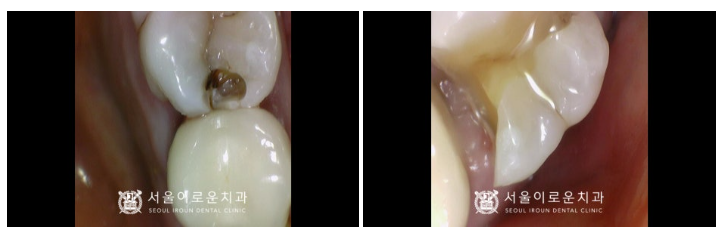

그리고 위턱 첫 번째 큰 어금니(#16)는

충치를 제거한 뒤 확인해 보았더니

치아에 금이 관찰되어

처음 계획했던 인레이 진행이

어려울 것으로 판단되었는데요.

신경치료 + 크라운 수복으로

계획을 변경하였고,

뿌리 끝까지 깔끔하게

신경치료를 마무리한 뒤

크라운 수복까지 성공적으로 도와드렸답니다.

임플란트 / 신경치료 + 크라운수복

치료를 모두 마무리 한 모습입니다.